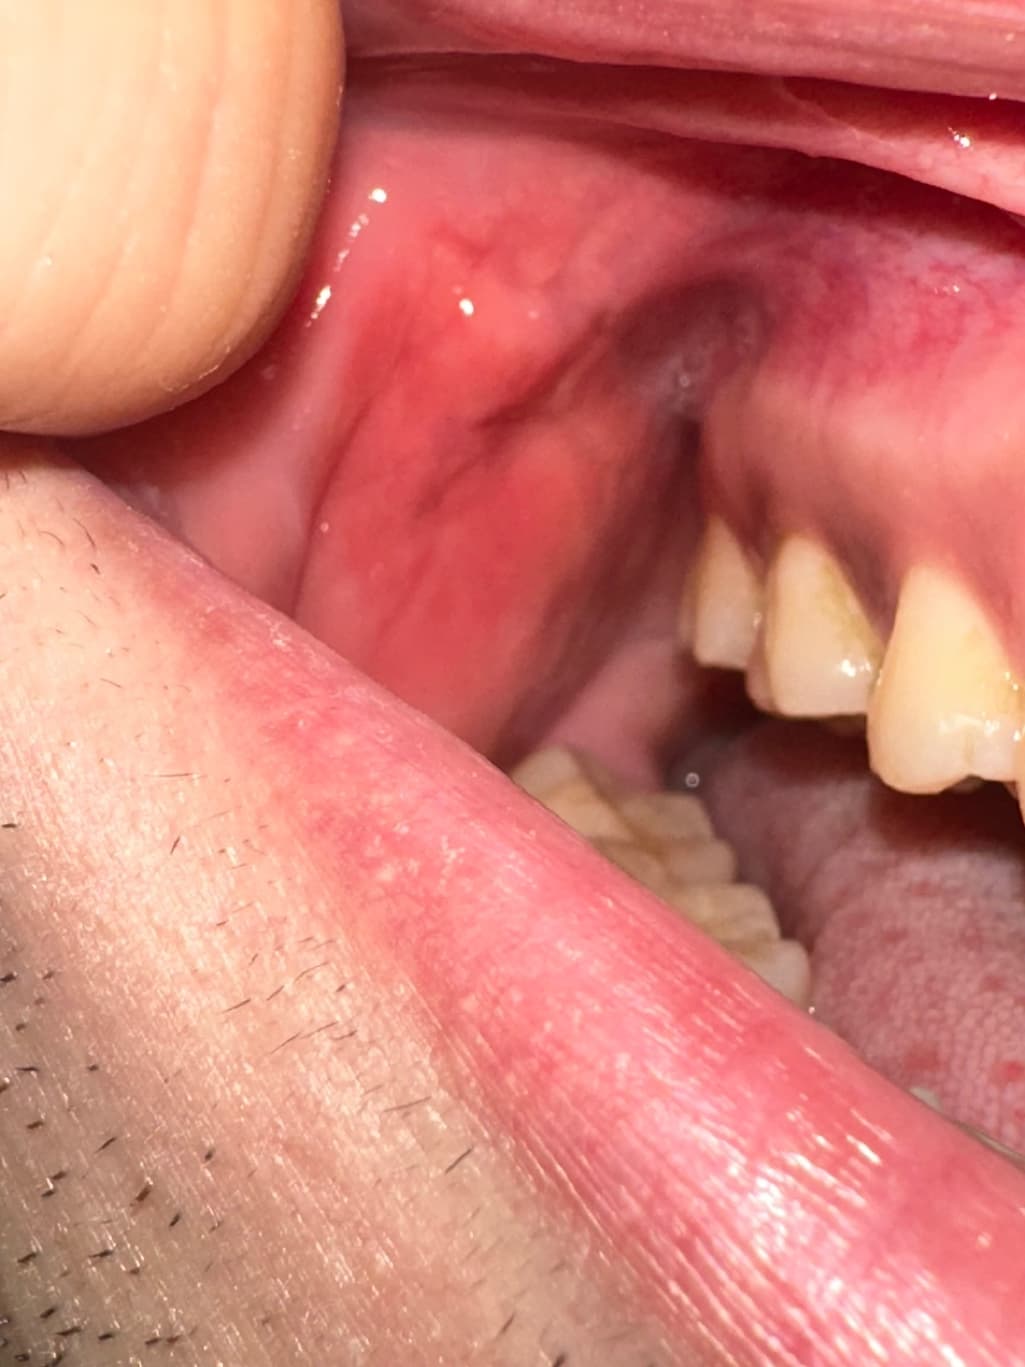

구강내 우측 상당 어금니 부분 옆 볼살에 이질감이 느껴집니다

안냥하세요 평소에도 좌측과 우측 동일하게 혹 비스무리흔디 잡히고 그랬었습니다 다만, 이틀 전 부터 우측 부분이 붓고 평소보다 살짝 더 심하게 느껴지는 것 같았슺니드 이게 정살일가료? 참고로 흡연 11년 하루 8개이며 나으ㅡㅡㅡㄷ

• 1번 째 사진